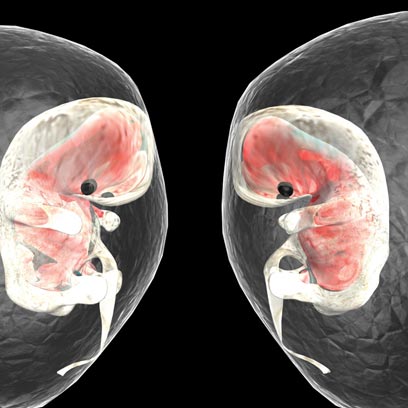

למרות ששיבוטים קיימים כבר הרבה מאוד זמן, טרם בא לעולם אדם משובט. כדי להבין למה, צריך להבין איך בעצם עובד הקונץ של השיבוט. האסטרטגיה היא כזאת: לוקחים תא אחד מהיצור המועמד לשיבוט ושודדים ממנו את הגרעין - החלק החשוב ביותר בתא, שמכיל את כל המידע הגנטי שמכתיב את תכונות היצור. בשלב הבא מחדירים את הגרעין לביצית שנלקחה מנקבה אחרת, ואז הביצית מתחילה להתפתח וליצור עובר שהקוד הגנטי שלו הוא זה שקיים בגרעין. עד 1996 האמינו שאי אפשר לשבט יונקים בדרך הזאת, ואז באה דולי, השיבוט הראשון של כבשה בוגרת. ומה אנחנו, עז?

העניין הוא שמכבשים לבני אדם הדרך עוד ארוכה. לא בגלל שבני אדם מסובכים הרבה יותר מיונקים אחרים, אלא בגלל העובדה שאנחנו הרבה יותר יקרים - וטכנולוגיות השיבוט הקיימות לא מספיק יעילות כדי להבטיח מאה אחוז הצלחה. בעצם, אפילו הצלחה של עשרה אחוזים תהיה שיפור ביחס למצב כיום; לצורך השיבוט של דולי, למשל, נדרשו לא פחות מ־276 ניסיונות כושלים.

גם בעידן הנוכחי, כשאפשר לשבט חתולים וכלבים, עדיין יש צורך בעשרות עד מאות ניסיונות כדי להביא לעולם שיבוט אחד מוצלח. ומכיוון שכל ניסיון לשיבוט אנושי יחייב שימוש במאות ביציות והשתלת כל אחת מהן אצל אם פונדקאית אחרת, צריך מדען ממש מטורף למשימה הזאת, שגם יצליח לגייס מימון לפרויקט העצום הזה. אגב, גם במקרה שיימצאו האיש והכסף זה לא ייגמר טוב. רוב מוחלט של הפונדקאיות צפויות לעבור הפלה ספונטנית ומסוכנת - או להתנחם בסיכוי הזעיר ללדת תינוק משובט, שכנראה יסבול מבעיות התפתחות בגלל הפרוצדורה המסובכת שחווה עוד כשהיה עובר בן תא אחד.